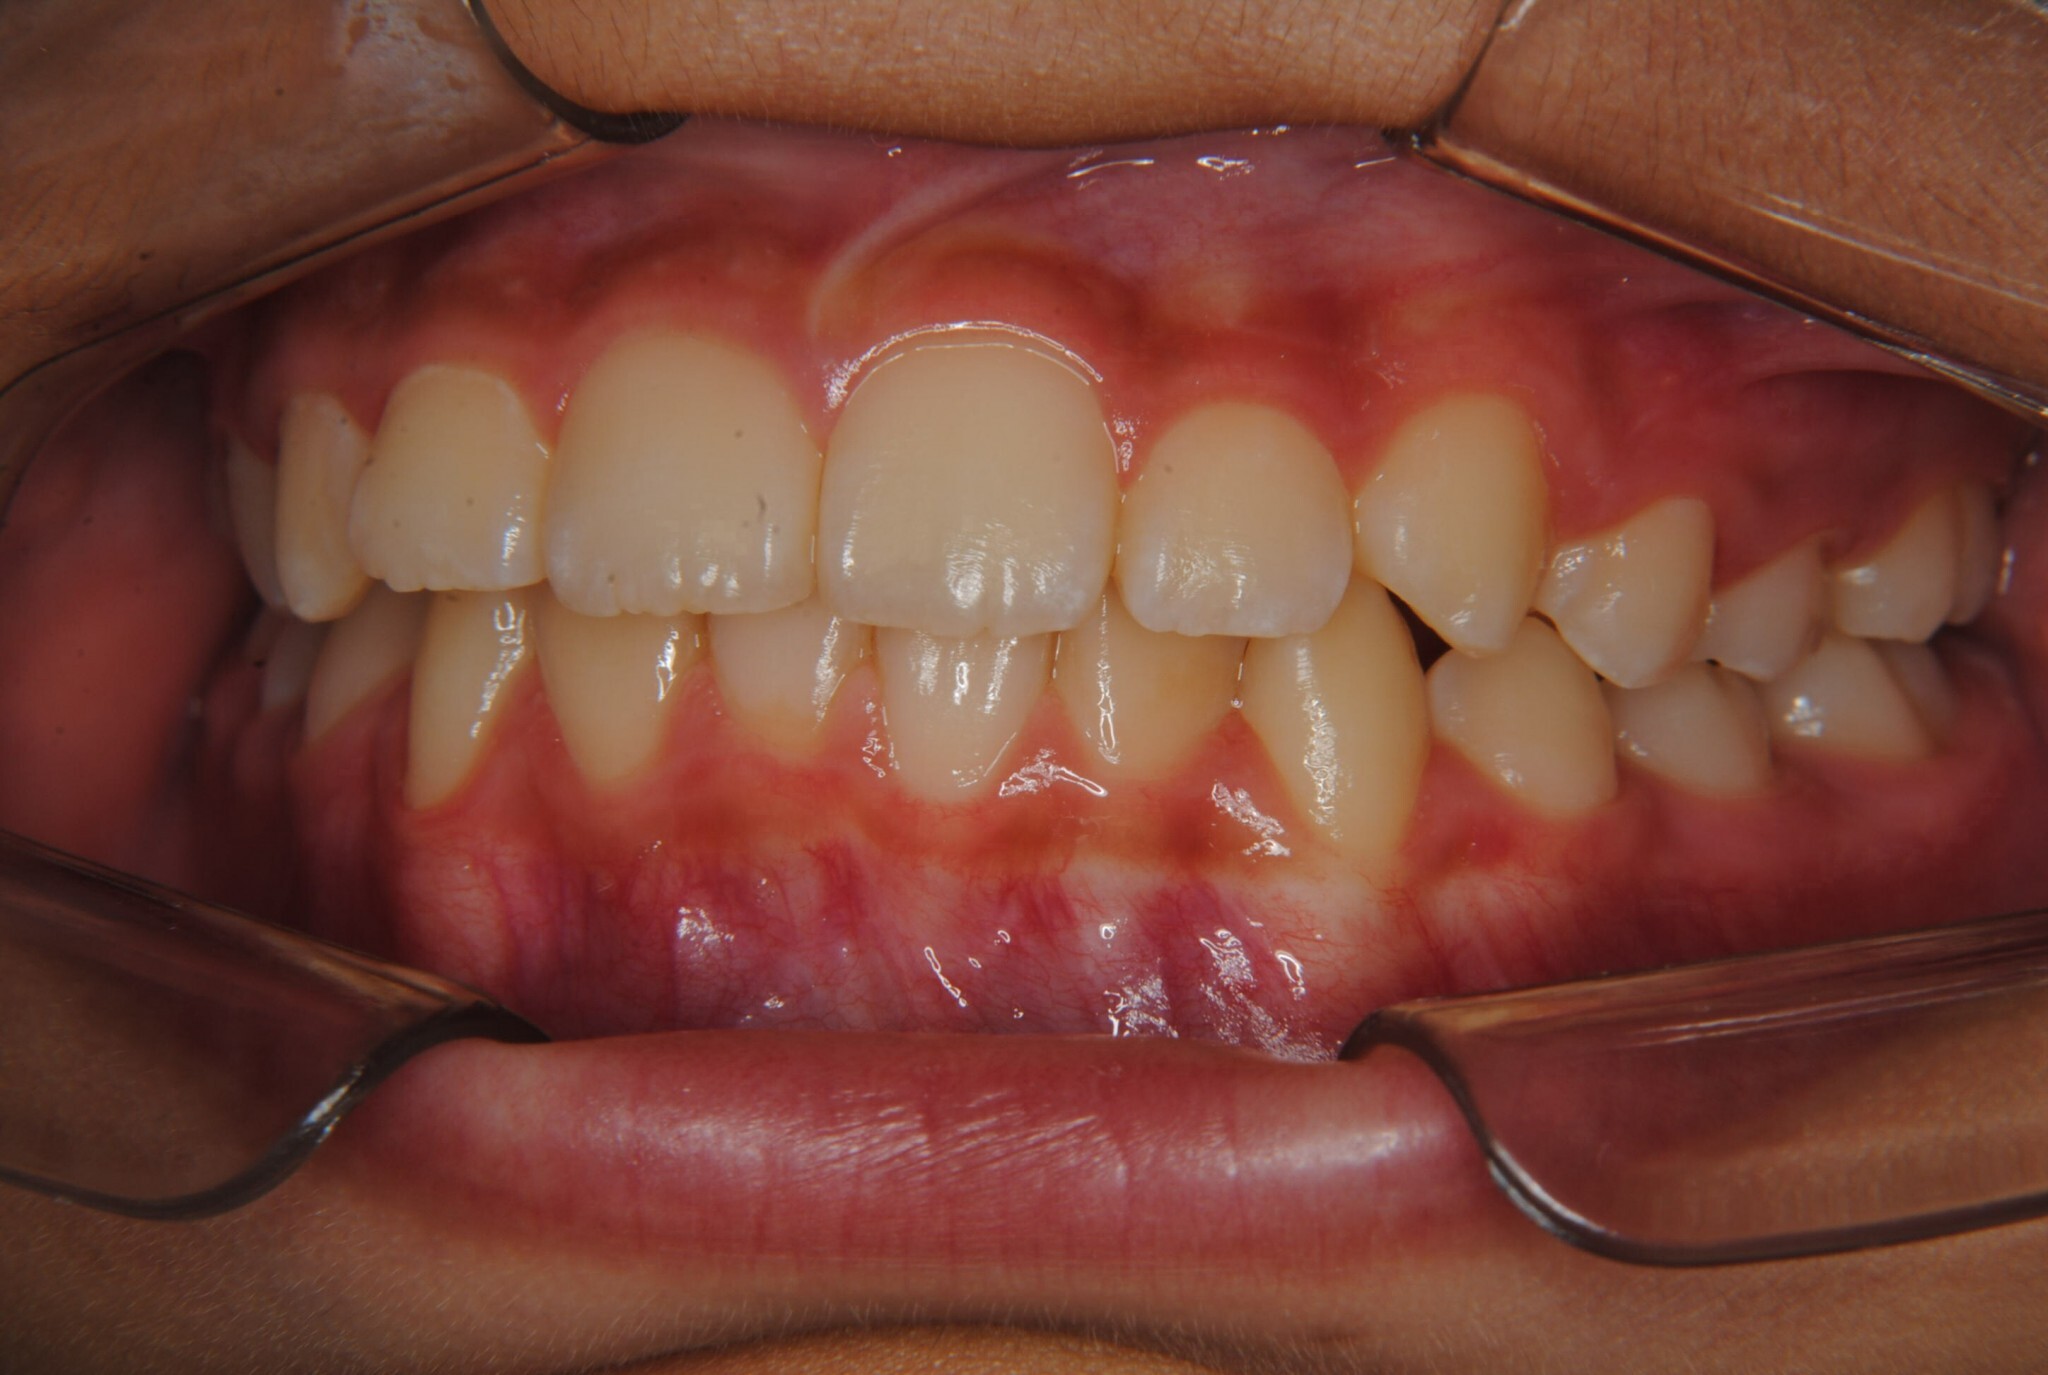

②診断名:Ⅰ級叢生

③年齢:初診時(左写真)8歳6か月、終了時(右写真)11歳4か月

④治療に用いた主な装置:拡大床

⑤抜歯部位:なし(非抜歯)

⑥治療期間:1年4か月

⑧リスクと副作用:特に大きなリスクや副作用はありませんでした。拡大床装着直後は違和感があったようですが、特に痛みを感じることなく6.5mmまで拡大できました。その後永久歯への生え変わりも順調で、ほぼ正常な咬み合わせになりました。この後11歳4か月まで観察し、7番目の奥歯である12歳臼歯がきちんと咬んだので終了となりました。